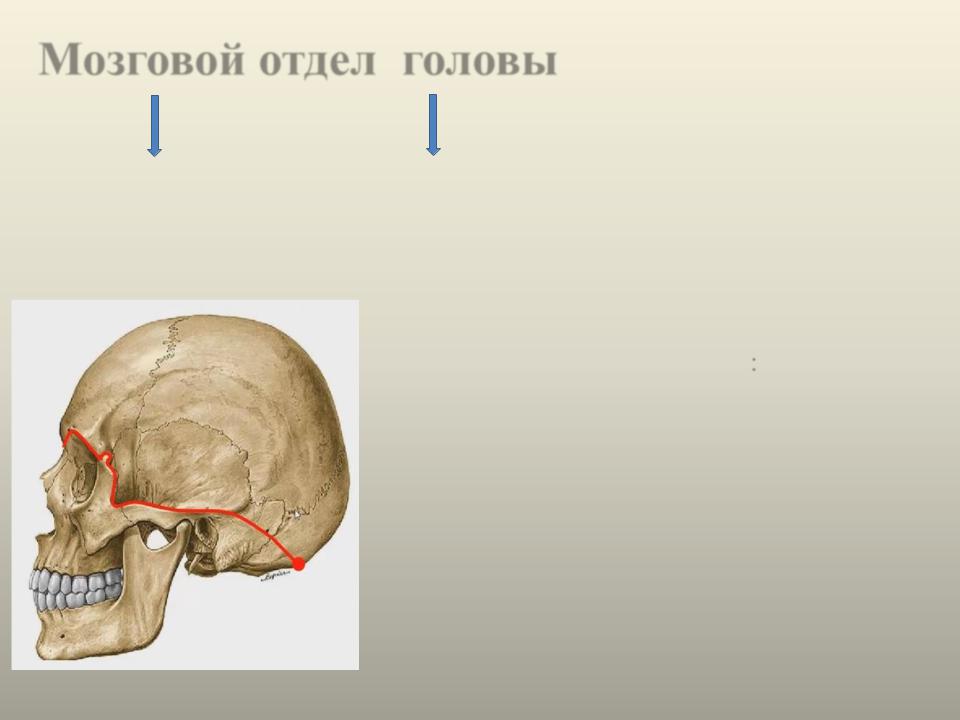

Анатомия сосцевидного отростка